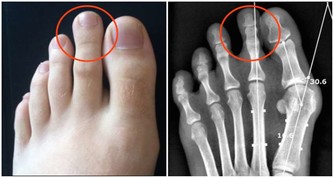

5、兩手、兩腿突然冰涼、發白髮紫、腳趾頭髮黑:

要考慮急性動脈栓塞。

提醒大家要儘早就診,錯過了黃金搶救時間,到了截肢這一步就回天乏力了。